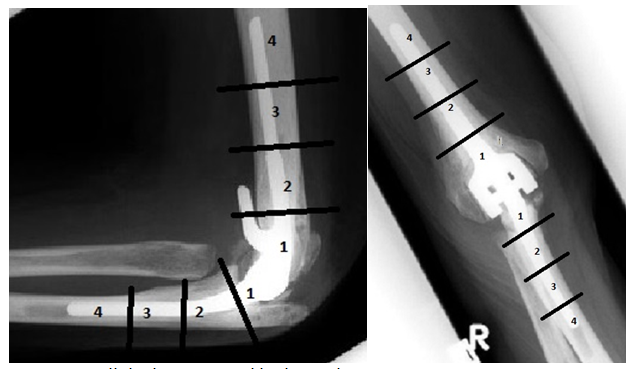

Plain radiographs were obtained for all the patients preoperatively and postoperatively and the severity of preoperative arthritic changes was graded from grade 1 to grade 5 as suggested by Larsen et al.10 The overall satisfaction in surgery results was categorized as follows: 4 – ‘very satisfied’, 3 – ‘satisfied’, 2 – ‘no change’, and 1 – ‘worse’. Pain severity in motion and at rest was assessed using a numeric rating scale from 0 – ‘no pain’ to 10 – ‘extreme pain’.11 Overall discomfort in an affected elbow was rated from 1 – ‘least’ to 4 – ‘worst’. Active elbow range of motion (ROM) was assessed before the surgery and 36 (up to 252) months later by a physiotherapist using a manual goniometer with 5-degree precision. To categorize the radiolucency observed in X-ray images, humerus and ulna areas were divided in four zones (Figure 1).

Of the patients, 21 (22%) had radiolucent lines in ulnar zone 1, 11 (12 %) in ulnar zone 2, seven (7%) in ulnar zone 3, and nine patients (10%) had radiolucent lines in ulnar zone 4. Respectively, 22 (23%) patients had radiolucent lines in humeral zone 1, 11 (12%) humeral zone 2, four (4%) humeral zone 3, and four (4%) patients had radiolucent lines in humeral zone 4.

In this retrospective study of 95 patients with Coonrad-Morrey prostheses, pain level as well as elbow function and range of motion were good at the end of 16-year follow-up. The overall complication rate was 19%. Radiolucent lines were seen in zones 3 and 4 (Figure 1) of both components indicating loose implants. Eight patients needed a revision surgery – a change of one or more prosthetic components. There were 12 periprosthetic fractures. Most of the fractures in condyle or olecranon process were treated conservatively. Three patients had deep infection but only one needed a two-stage revision. The generalisability of the results might be affected by the fact that this was a retrospective uncontrolled study amongst patients of a single university clinic. The sample was predominated by women. During the follow-up, medication or other treatments were not comprehensively recorded. The surgery records did not contain a comprehensive description of cementing technique, used cement, or plugs used in the operation. On the other hand, this study employed the rare opportunity to observe the survival timeline of Coonrad-Morrey arthroplasty for over 15 years using a reliable source of information – electronic patient records created in a university clinic.